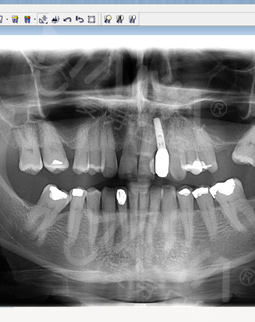

2016年4月 牙槽骨严重缺损,不适合一期种牙

来到深圳,多方寻医,一个医生朋友告诉我,这个只有到麦芽找郑苍尚院长,他能做。“我有6个月一直没有牙齿,我要我的牙齿。”这是我见到郑院长后说的第一句话,在麦芽流程很顺利,经过拍片检查后,郑院长说我剩余残根反复发炎松动,牙槽骨受损严重,影响咀嚼功能,只能拔除残根后需引导骨组织再生,不能一期种牙....很专业的词我不太懂,但是他能处理我就放心了!

在郑院长的建议下,我选择了诺贝尔植体,种植牙还需要骨粉骨膜,大致了解了种牙的流程,我很满意。